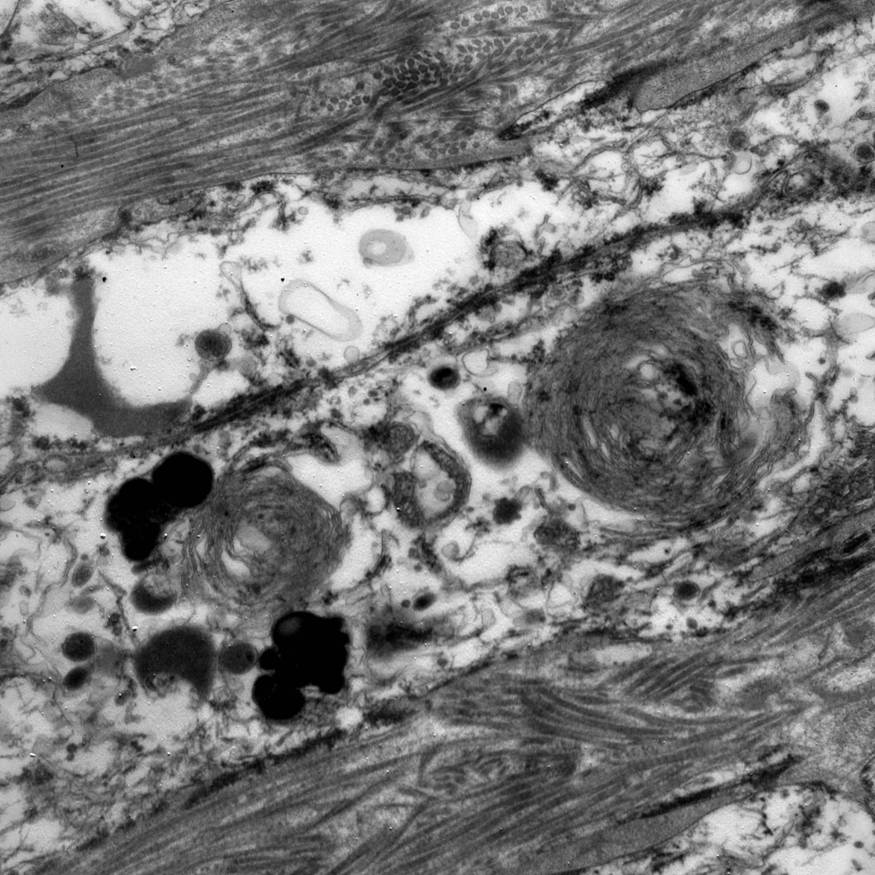

Electron microscopy description

- Abundant intracytoplasmic lipid droplets of varying sizes

- Prominent microvillous projections along cell borders

- Abundant smooth endoplasmic reticulum

- Prominent, round to oval mitochondria; cristae may have tubular to vesicular (zona fasciculata) or lamellar (zona reticularis) profile